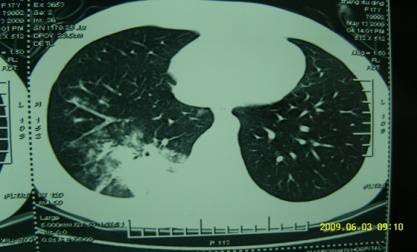

提问:高烧不退伴咳嗽10余天。病情描述(主要症状、发病时间):高烧39度伴咳嗽,无痰,57日,突然高热,无其他阵发性咳嗽,咳嗽时腰痛厉害。阿莫仙、阿奇,现用美平静滴,体温不降。中药吃了2付。血沉110 CRP112,其他均在正常之内,CT:右下肺炎症。

治疗前

按:急性重症肺炎中期、极期的肺部影像学特点绝大部分患者出现弥漫性肺部炎症异常表现。病变形态分为斑片状影,大片状影,斑片融合影像。病变密度为肺实变密度及磨玻璃密度影,肺纹理增粗模糊,肺实变的影像和临床表现相关联,持续高热时,肺部影像最为严重和广泛。此时西医治疗要点:要及时适量、足量使用糖皮质激素。中医辨证:疫毒犯肺,邪在气分。治则:清瘟泻热解毒,宣肺平喘。中西医结合治疗,短期内炎症吸收迅速,病情好转,没有遗留,邪去正安。